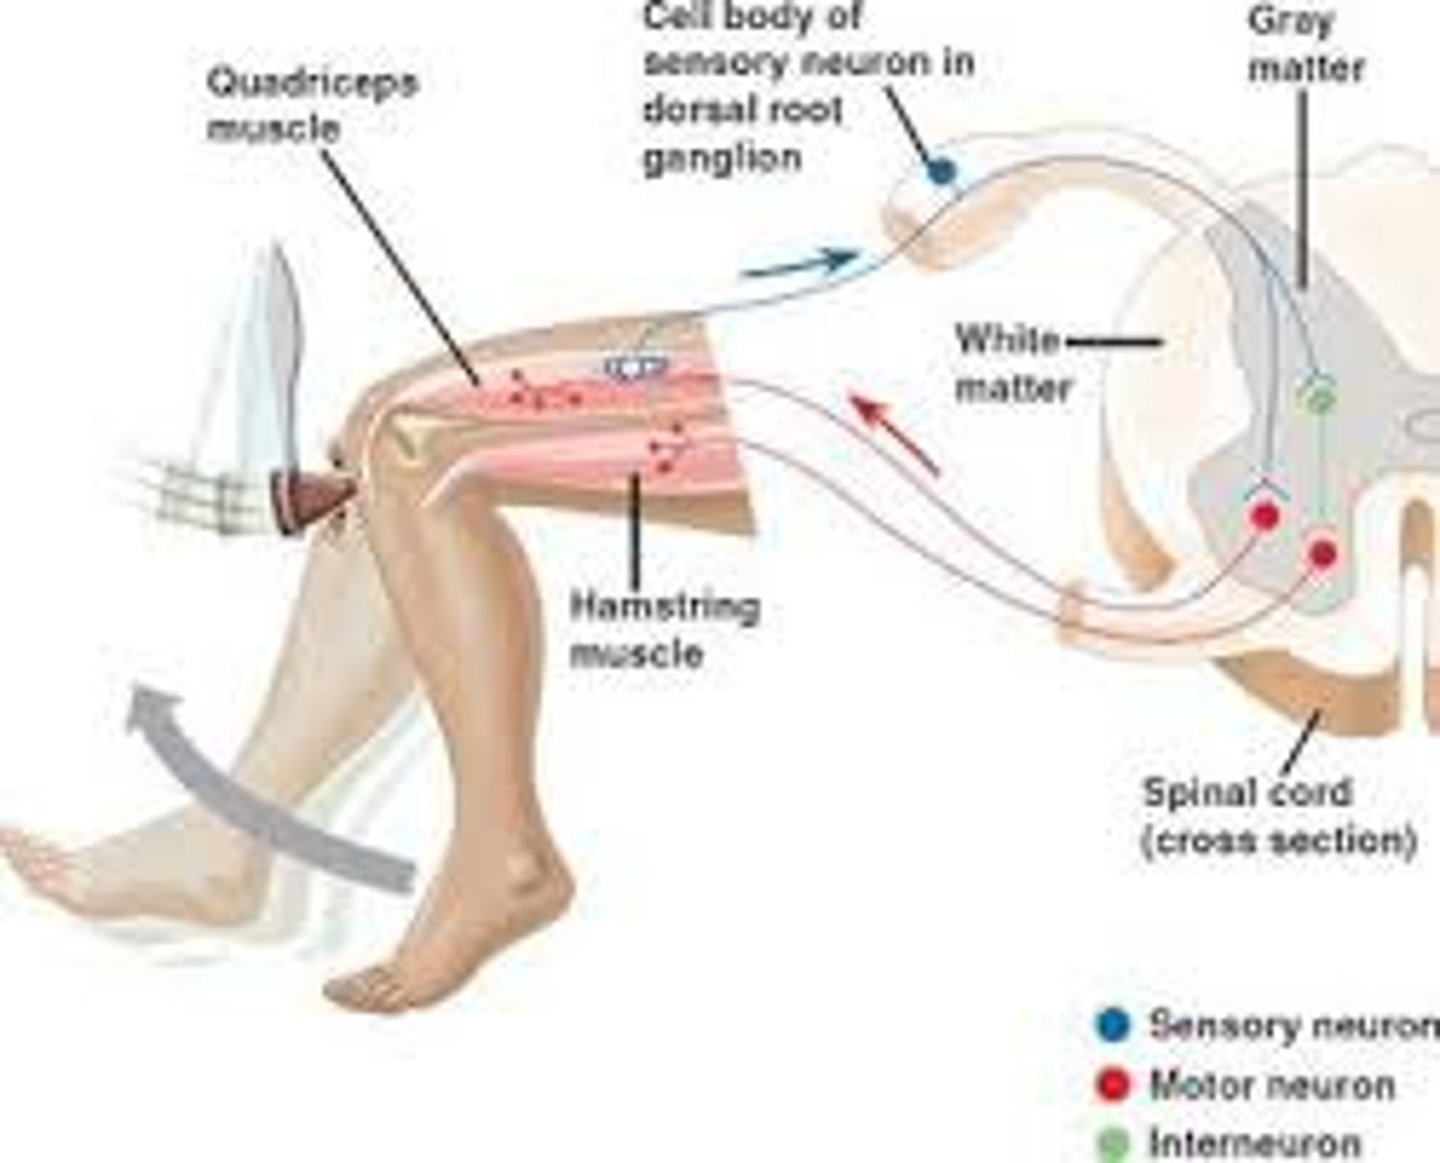

Reflex arc

a relatively direct connection between a sensory neuron and a motor neuron that allows an extremely rapid response to a stimulus, often without conscious brain involvement

Interneurons

neurons that transfer messages to other neurons nearby

Sensory neurons

neurons that carry incoming information from the sensory receptors to the brain and spinal cord

Motor neurons

neurons that carry outgoing information from the brain and spinal cord to the muscles and glands